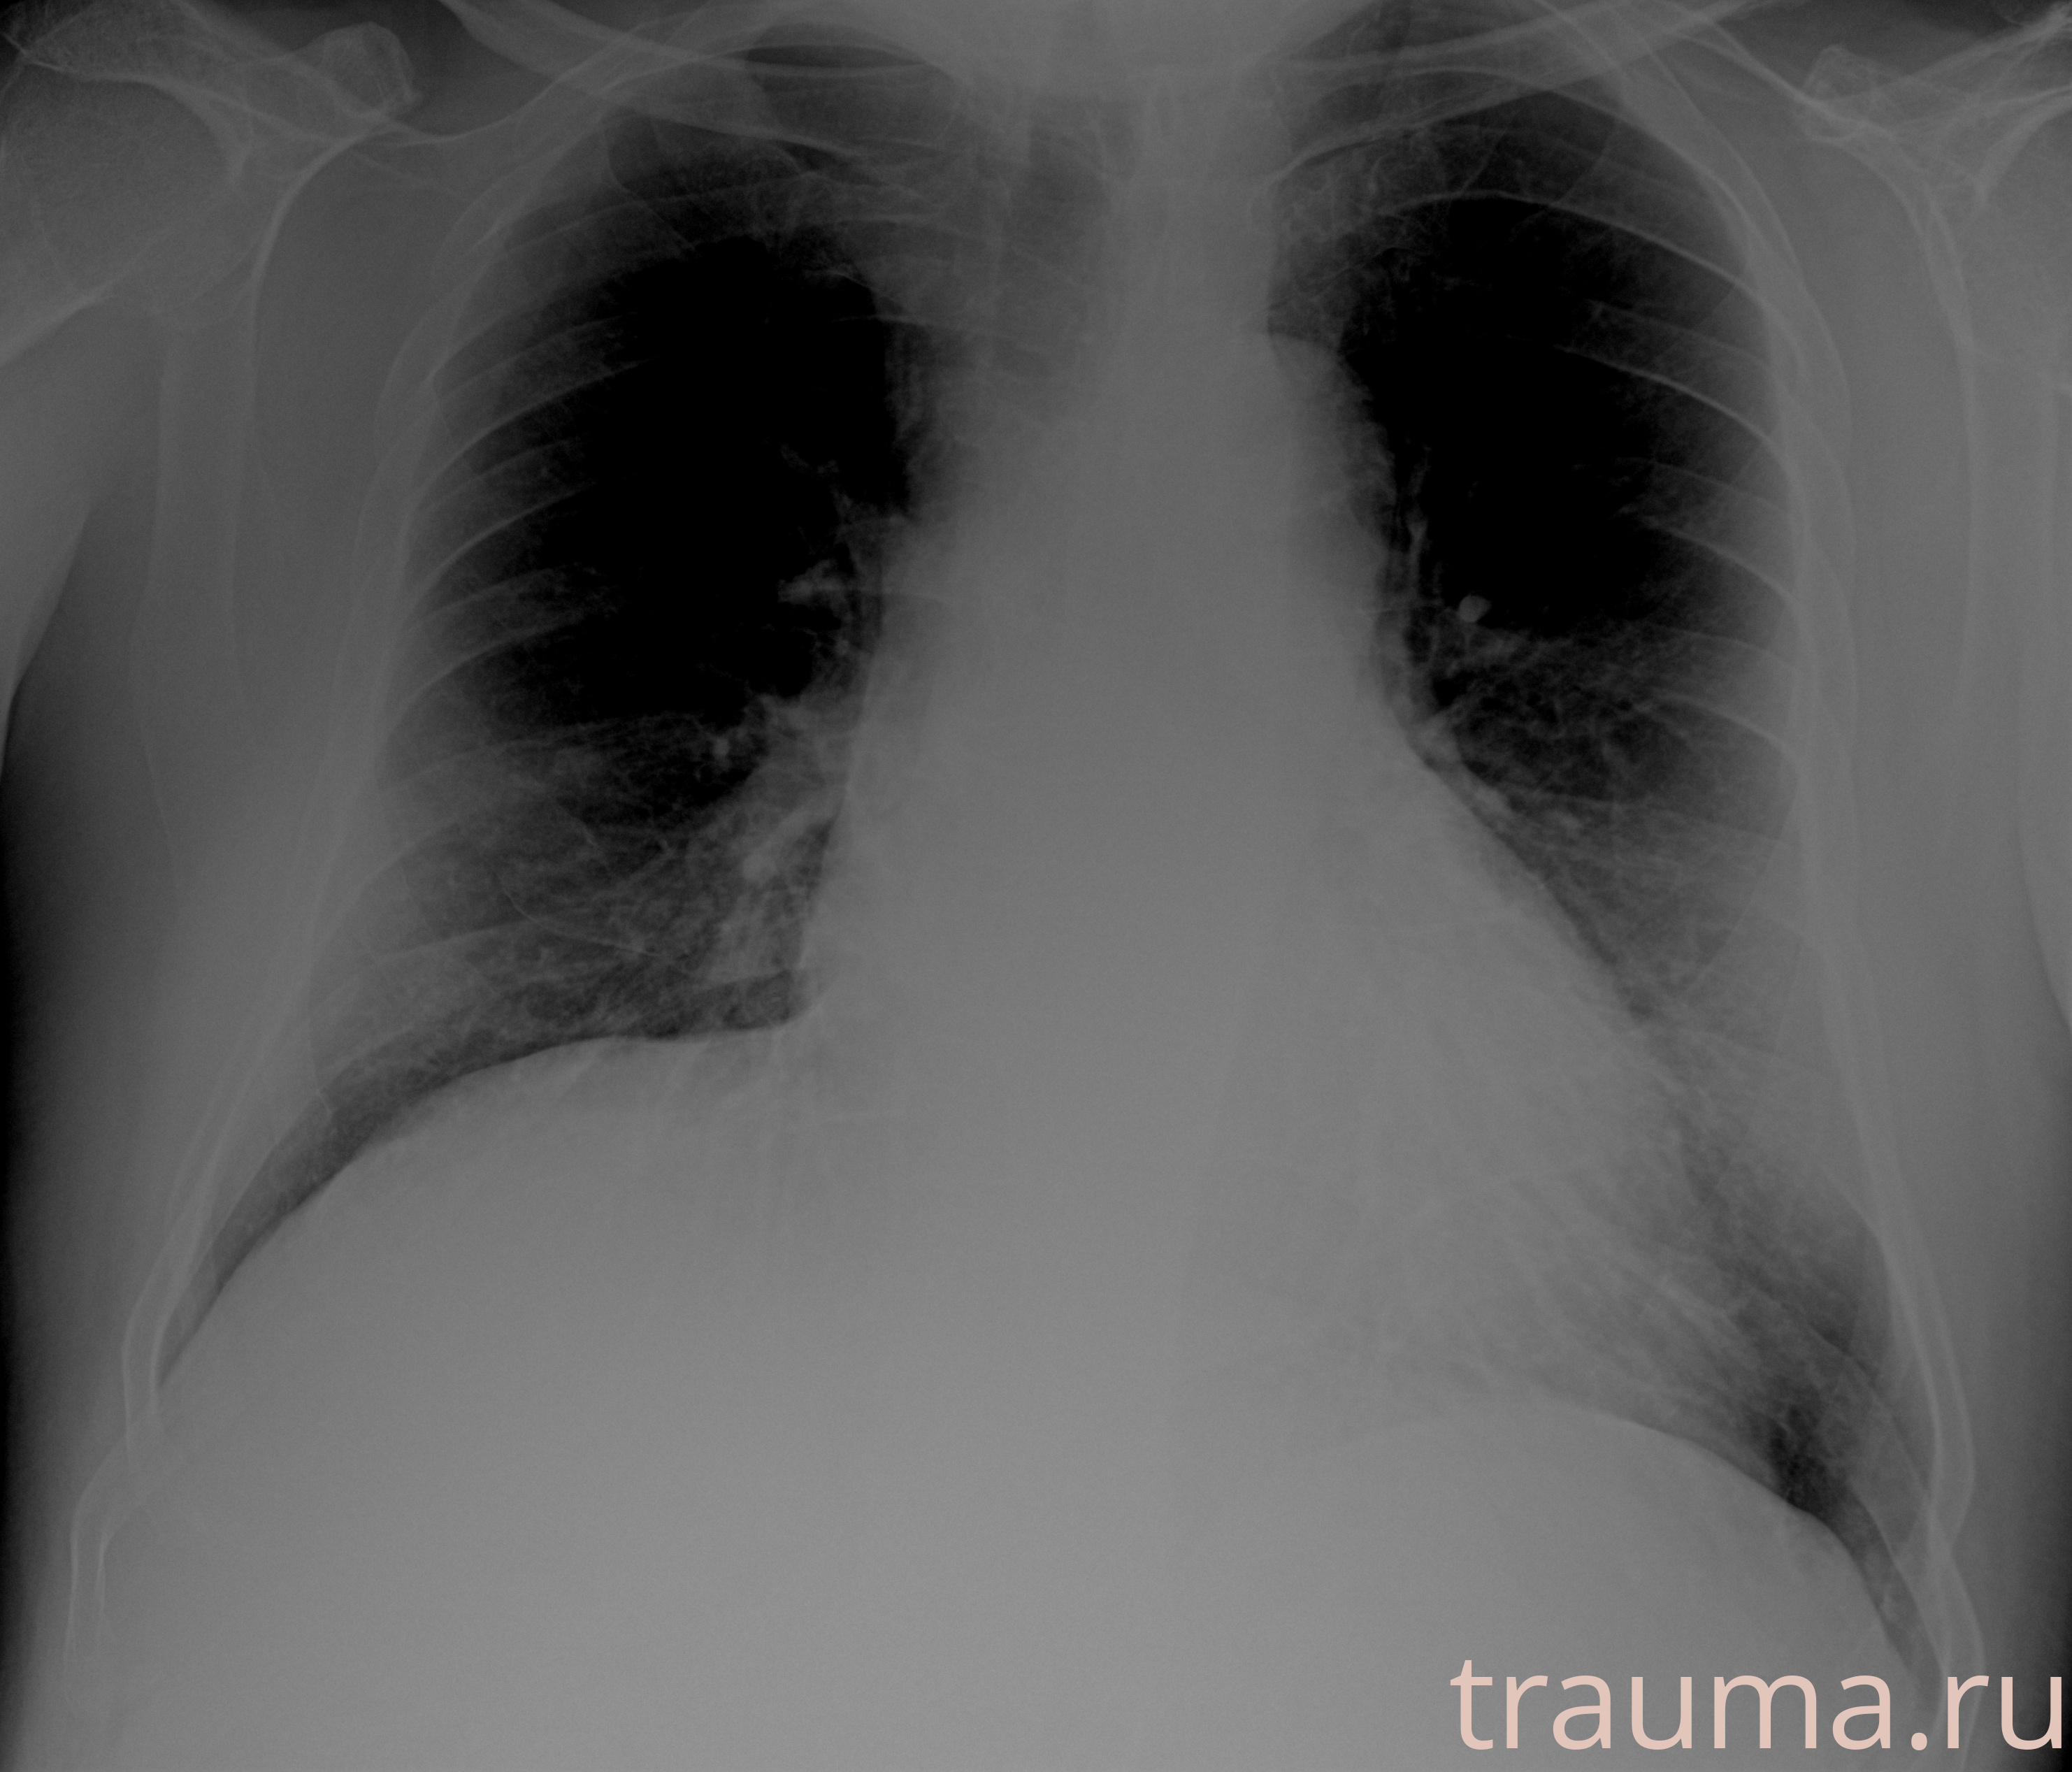

Рентгенограммы

Рентген на дому: по вашему адресу приезжает врач-рентгенолог, травматолог-ортопед с мобильным рентгеновским аппаратом, проводит диагностику травмы или заболевания, делает необходимые рентгенограммы, дает рекомендации по дальнейшему лечению. Получить качественные снимки в домашних условиях возможно благодаря уникальной методике, разработанной МосРентген Центром для института  Склифосовского

Яркость: 1   Контраст: 1   Инвертировать: 0 Увеличение: 1

Перетаскивайте мышь вверх/вниз для контраста, влево/право для яркости. Прокрутка колесом изменяет масштаб. Нажмите Сбросить для возврата к исходному изображению. При увеличении держите мышь в той области, которую хотите рассмотреть.

при переломе шейки бедра и пневмонии от компании МосРентген Центр - партнера Института имени Склифосовского